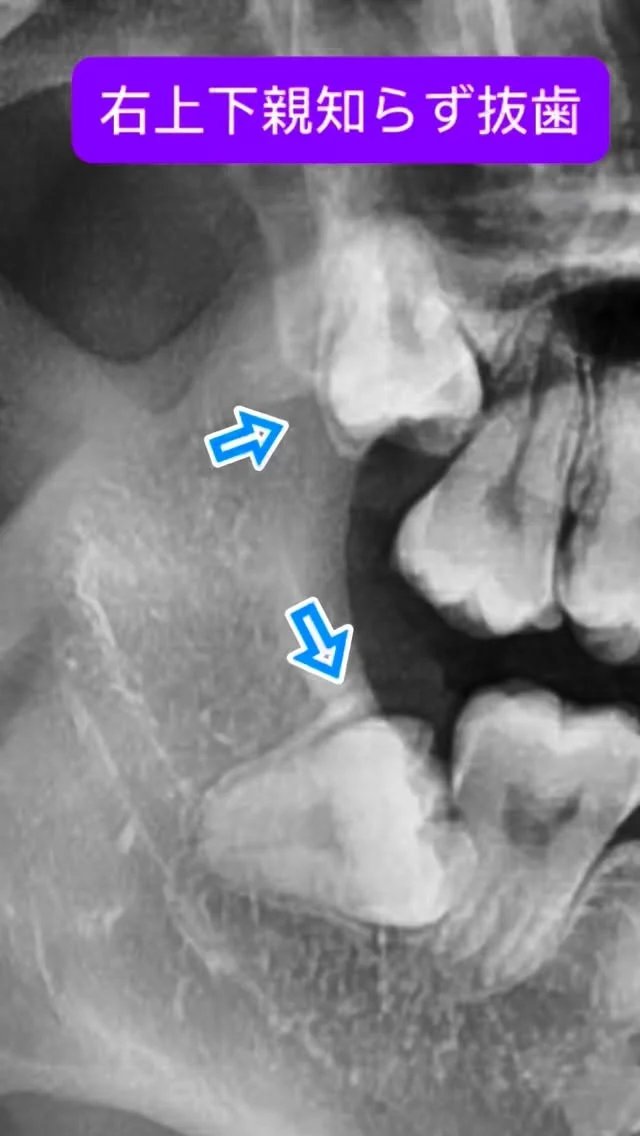

大学病院や総合病院で長年、親知らず抜歯や歯根端切除術などの小手術から、全身麻酔下で行う顎矯正手術(骨切り)、口腔腫瘍、インプラント治療など幅広い口腔外科診療・手術に携わってきました。

これまでに数多くの難症例を担当し、「安全、スピーディーかつ合併症を低減する手術」を常に意識してきました。特に骨切り手術では、機能面の改善だけでなく、顔貌のバランスや審美性にも配慮し、口元の自然な美しさを追求しています。

日本口腔外科学会専門医、日本顎変形症学会認定医など、多くの専門資格を有し、先端の知見と技術に基づいた治療を提供します。

親知らずや顎の形のお悩み、外科的な処置に不安をお持ちのかたも、ぜひ一度ご相談ください。専門医として、丁寧に寄り添いながら適切な治療をご提案いたします。